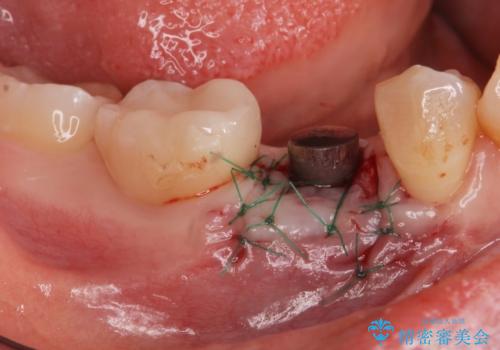

インプラント治療

- 過去に抜けてしまった歯のところにインプラントを入れたいとの事で来院。

CTで確認したところ骨の高さや厚みがインプラント埋入できる状態でしたのでインプラント治療を行いました。

併用して銀歯も気になるとの事でしたのでセラミック治療も行いました。